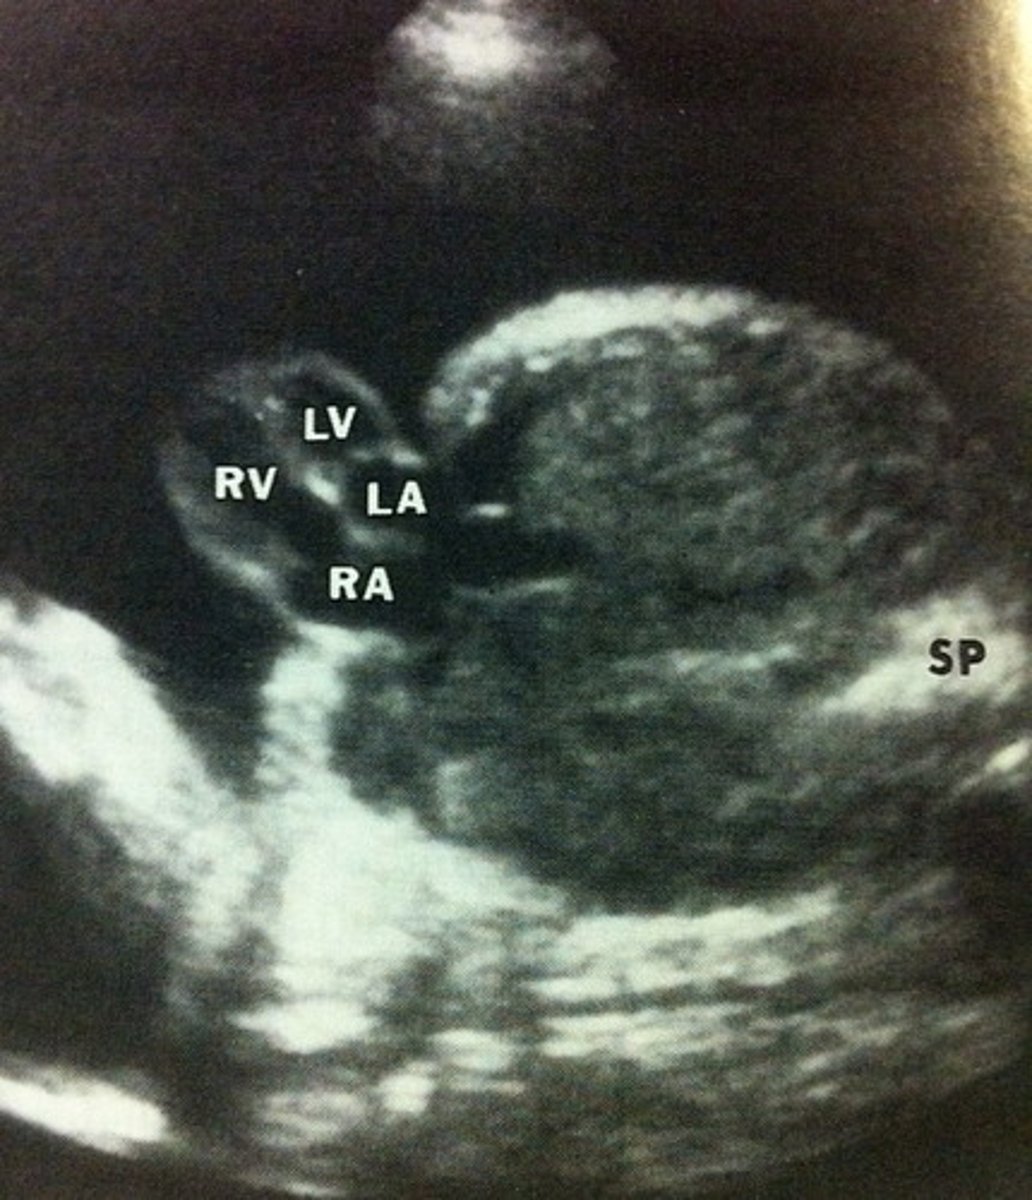

VSD

Most common cardiac defect

Best seen in LVOT view or 4ch. if septum is perpendicular to sound beam

Hole in ventricular septum

Commonly in membranous septum